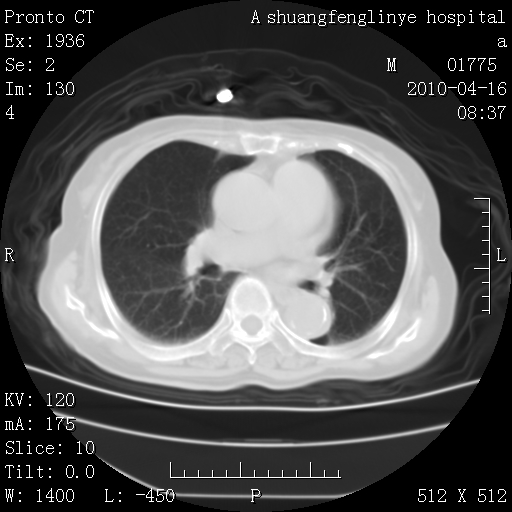

老年肺间质纤维化,肺动脉高压-----肺心病。

慢支肺气肿,左上陈旧性结核,主动脉冠脉钙化

1)左肺上叶结核(纤维、增殖病灶)。2)冠状动脉及主动脉钙化。

1)左肺上叶结核(纤维、增殖病灶)。2)冠状动脉及主动脉钙化。肺动脉高压